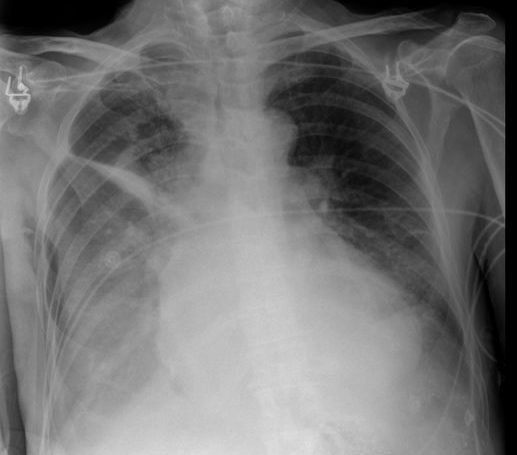

Fibrosis pulmonar. ICC.